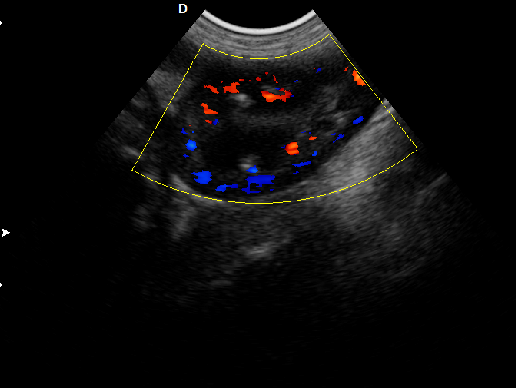

P5-VET獸用彩超機出色的獸用臨床應用

P5-VET高清便攜式獸用彩超機是一款高清晰度,功能全面的彩色多普勒獸用超聲診斷儀,它可以滿足滿足寵物醫院及科研機構在消化系統、生殖系統、泌尿系統、體檢及其它方面的檢查和診斷。